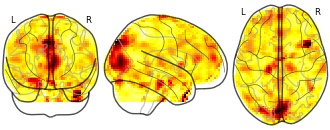

"name": "VBM_HeterogeneityMap",

"description": "Abnormal gray matter in BPD. Brain regions with significant heterogeneity (i.e. between-study variance) in the comparison of patients with BPD and healthy controls. Results are thresholded at at p<.005 & k>20. Note: Results are based on meta-analysis of group comparisons. Note2: Results were updated (see Erratum for this publication)",

"add_date": "2016-01-21T18:23:32.131003+01:00",